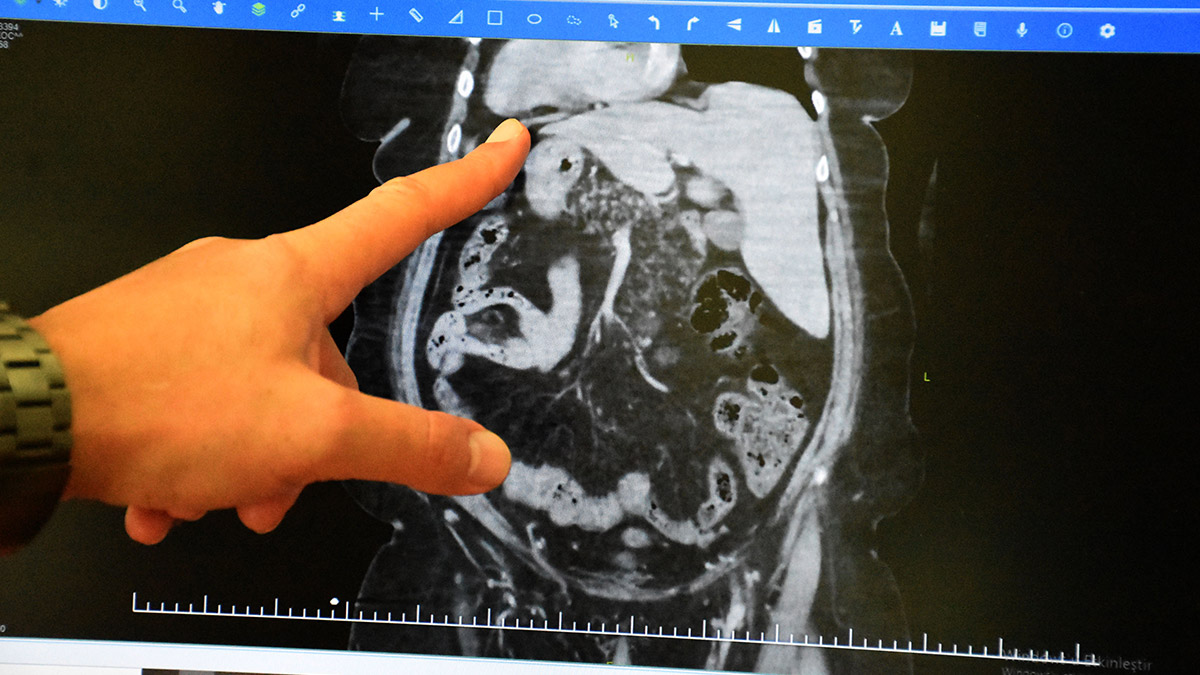

Ameliyatla ilgili bilgi veren Dr. Gündüz Akgöl, “Hastamızın özel bir durumu vardı. Doğuştan göğüs ve karın içindeki organların tamamen ters yönde yerleşimliydi.

Normal insanlarda kalp solda olur ama bu hastamızda sağda. Karaciğer ve safra kesesinin sağda yerleşimli olması lazım. Bizim hastamızda sol tarafta. Dalak ise solda olması gerekirken sağda. Hastamız bu durumunu daha önceki yapılan tetkiklerde saptandığı için biliyordu. Bu hastamız safra kesesinde taşa bağlı karın ağrısı şikayetleriyle bize başvurdu.

Safra kesesinde taş olması nedeniyle ameliyat planladık. Ameliyat hazırlıkları sırasında literatürü taradık. Bu organ tersliği durumu yaklaşık 30 bin kişide bir görülen çok ender bir durum. Bu hastalarda safra kesesi taşı olması da çok nadir görülen bir durum. Yine literatürü taradığımda 80 tane organları ters hastaya kapalı safra kesesi ameliyatı yapılmış.

Bugüne kadar dünya genelinde yayına geçen 80 tane hasta görülüyor. 2014 yılında bu ameliyattan bir tane daha yapmıştık. O zamanlar yayınlanan 40 hasta vardı. Son 8 yılda bu literatüre 40 hasta daha girmiş. Bizim hastamızda bu aşamada 81’inci oluyor. Bu hastamızın organları ters olduğu için şimdiye kadar yaptığımız tüm ameliyatlardan farklı olarak kapalı ameliyatta aletlerin yerleri değişti. Kullandığımız cihazların konumları biraz bizi zorladı.